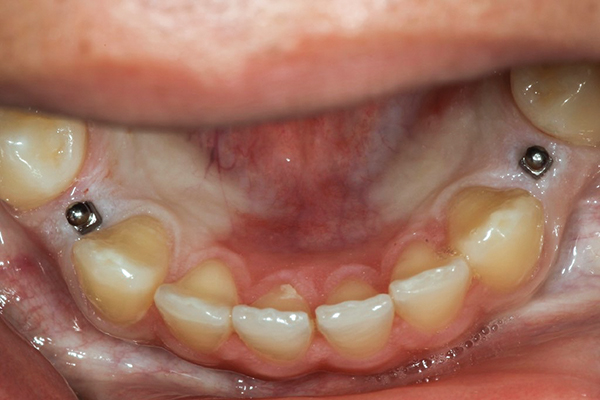

Evaluarea dentiției antagoniste a obiectivat absența dinților posteriori superiori stângi (segmentul 2.5.-2.8.), fiind restaurați prin proteză parțială mobilizabilă. După ce pacienta a acceptat tratamentul implicând MISFR, s-au inserat chirurgical două mini implanturi de 2,4 x 10 mm, în conformitate cu instrucțiunile producătorului, într-o manieră fără lambou (fig. 2).

După cele patru luni necesare osteointegrării mini implanturilor, s-a urmat un protocol standard pentru realizarea coroanelor metalo-ceramice conjuncte (porcelain-fused-to-metal, PFM). Restaurarea a fost cimentată cu ciment ionomer de sticlă modificat cu rășină, insolubil în apă. La examenele de monitorizare (fig. 3), s-a constatat că MISFR era funcțională de peste 6 ani, fără nicio complicație.